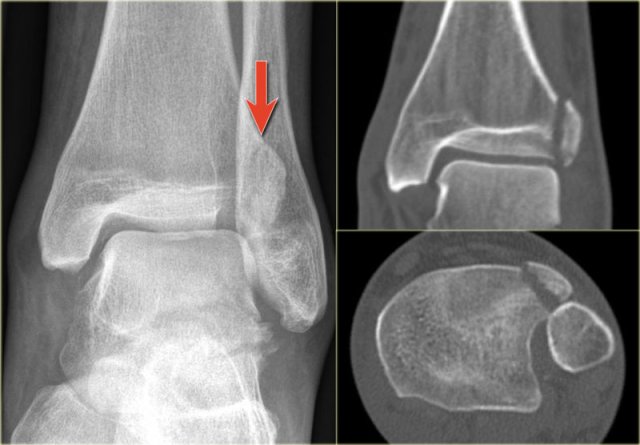

The x-ray shows a subtle Tillaux fracture, which is better appreciated on the CT-images.

Study these images carefully and remember the stages of an exorotation injury.

What is going on here?

There is a Tillaux fracture due to avulsion of the anterolateral part of the distal tibia by the anterior syndesmosis.

This can be a stage 2 of a Weber C fracture.

Stage 1 is rupture of the medial collateral ligaments and stage 3 is a fibula fracture above the level of the syndesmosis.

So now we start looking for stage 4, which is rupture or avulsion of the posterior syndesmosis.

Do you now see the tertius fracture on the axial CT-image?

This patient has an unstable ankle injury and a syndesmotic screw needs to be inserted.

There is a subtle widening of the lateral part of the growth plate of the right ankle.

There is also a very subtle fracture through the epiphysis.

Continue with the CT.

The CT-images show a epiphysiolysis fracture Salter Harris type 3.

This juvenile Tillaux is especially seen in young athletes.

Always look for higher stages of an exorotation injury.